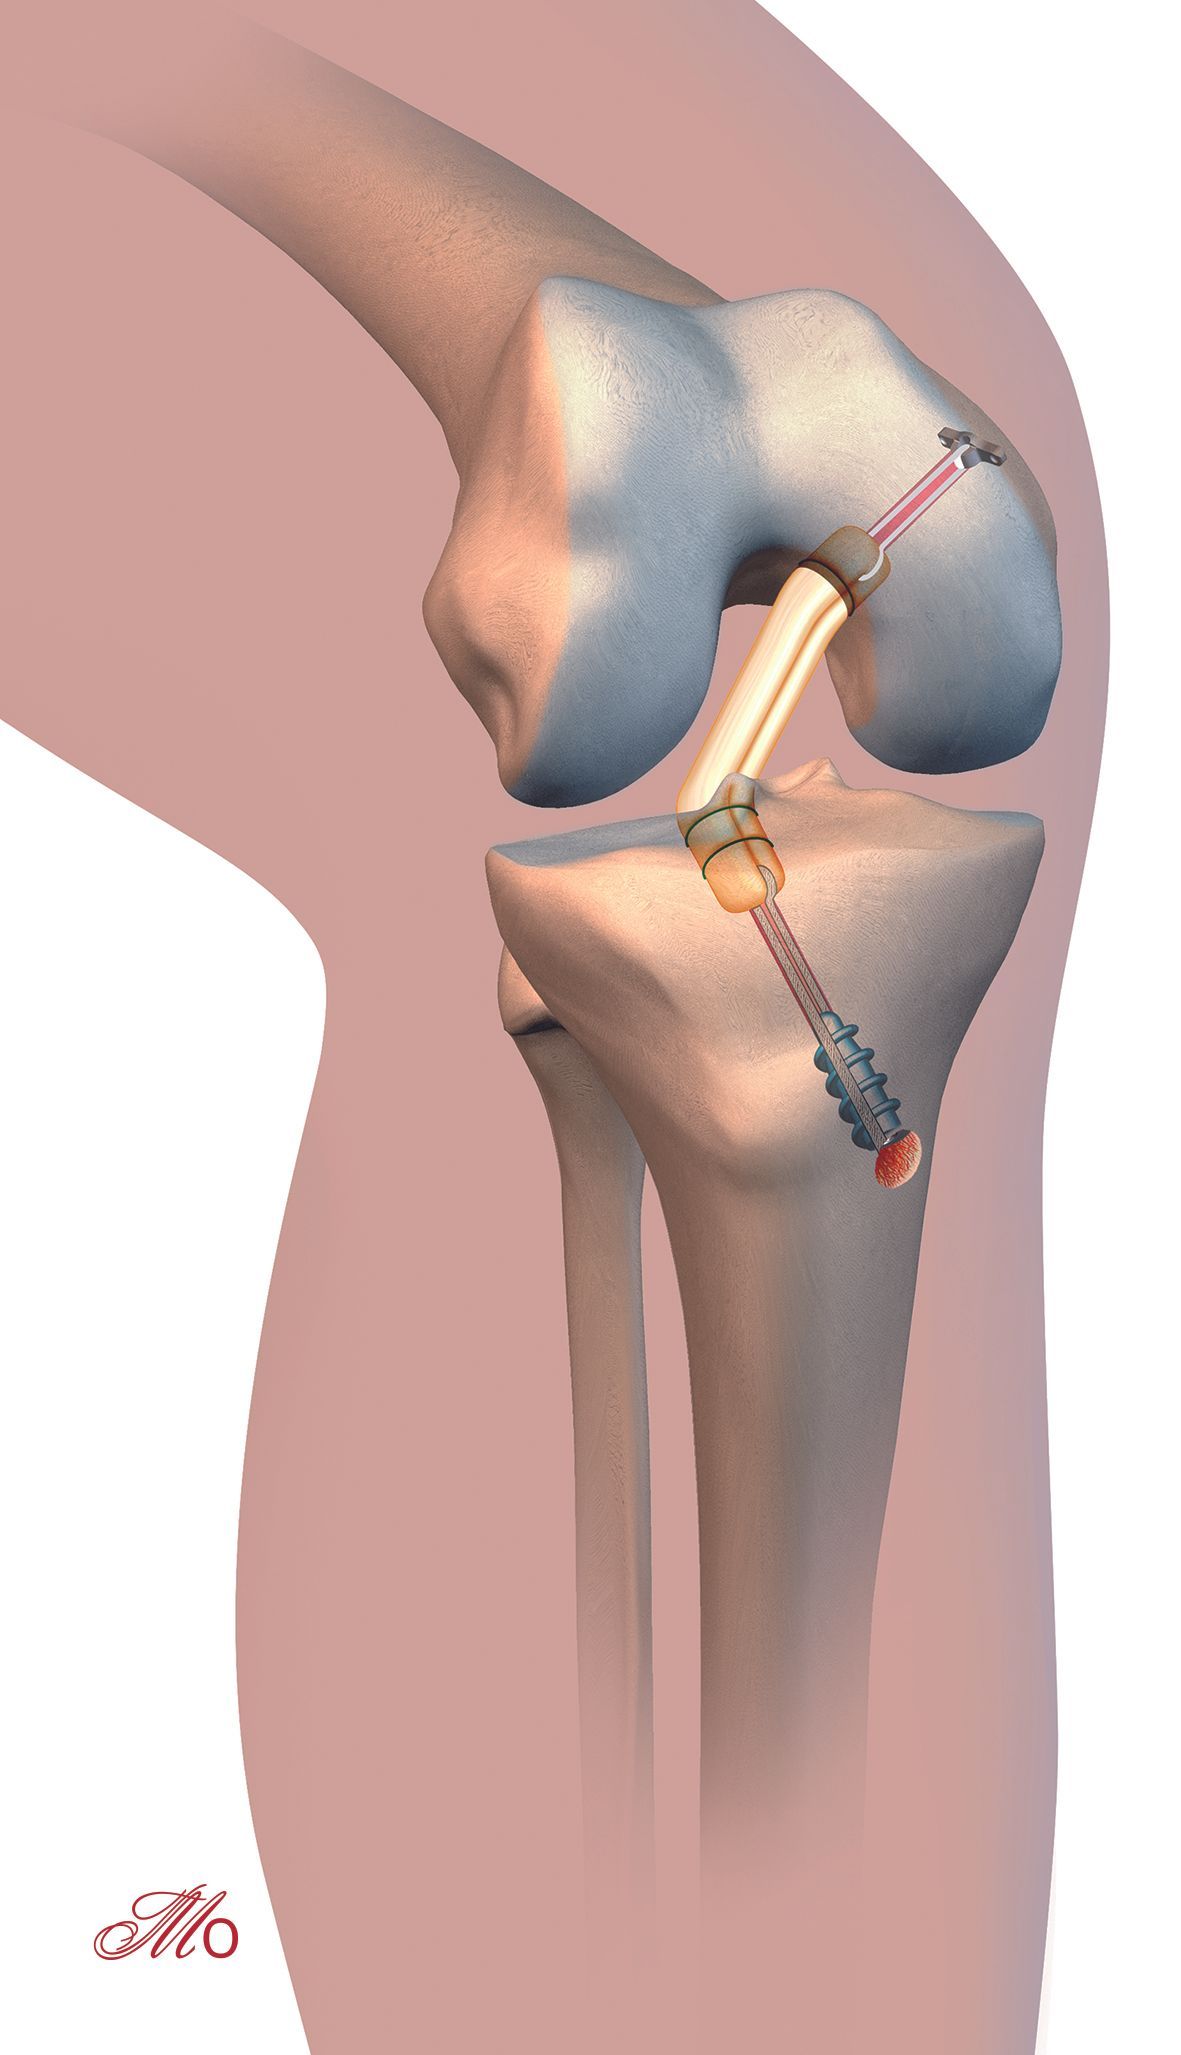

Technique Reconstruction du ligament croisé antérieur et arthroplastie unicompartimentale du genou , Marco Tinius Centre de chirurgie articulaire / Groupe du genou, Praxisklinik-Stollberg, Allemagne 🖂 marco.tinius@praxisklinik-stollberg.de , Stefan Klima Service d'orthopédie, de traumatologie et de chirurgie reconstructrice, Université de Leipzig, Allemagne , Timo M. Ecker Service de chirurgie orthopédique, Hôpital universitaire de Berne, Suisse N°258 Cahier 2 - Novembre 2016 ● 28 min de lecture